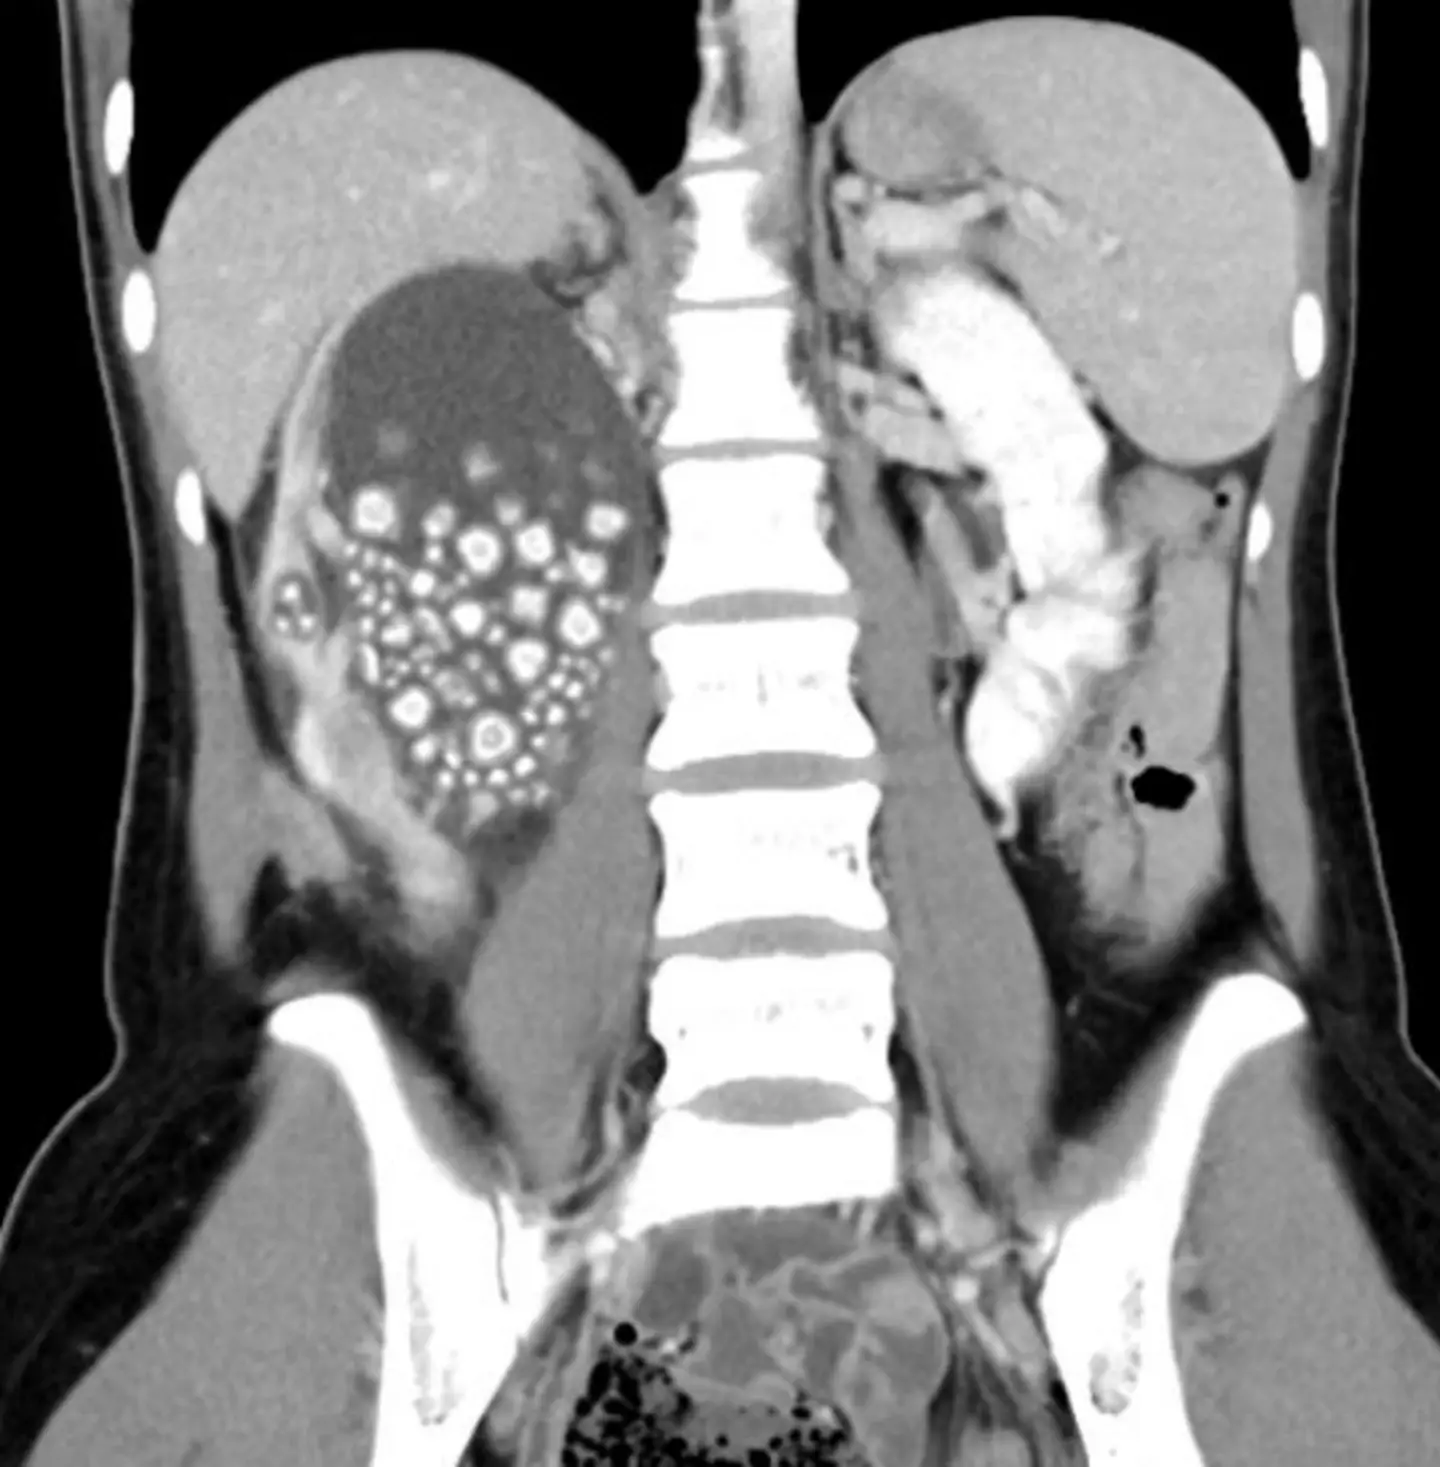

It explained how through the use of an ultrasound carried out by an emergency physician, the clinic discovered a severely swollen right kidney carrying hundreds of kidney stones.

Next, a computed tomography scan revealed that the center of the pelvis was filled with stones ranging from as small as half a centimeter to as large as two centimeters.

Dr Lin Caiyang, from the hospital's Department of Urology, was called in to perform minimally invasive percutaneous nephrolithotomy and successfully removed more than 300 kidney stones, the center reported.